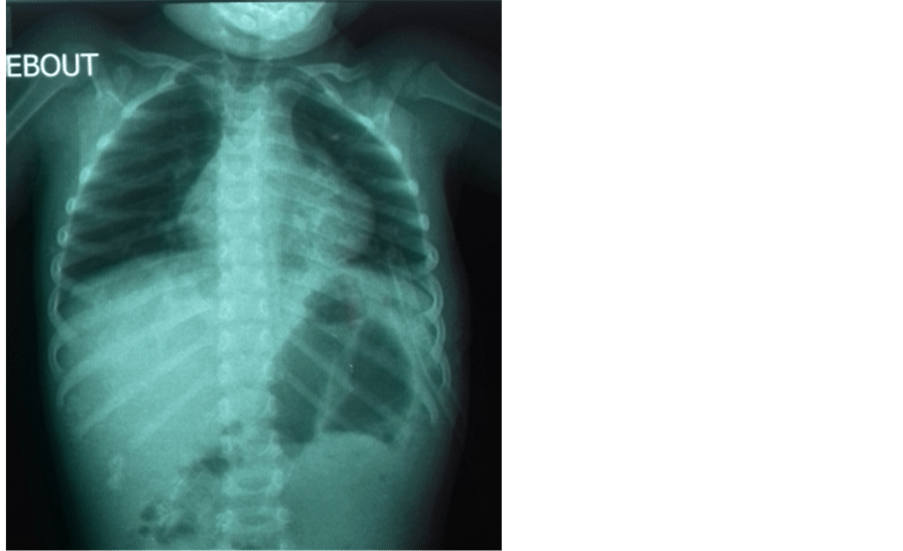

Paediatric chest Xray 01 Stock Photo Alamy Can You Breastfeed After Chest X Ray Where possible x rays are avoided during pregnancy but there is no reason to avoid them during breastfeeding. Breastfeeding should not be interrupted after gadolinium administration. We can say unequivocally that, given the risk of interrupting breastfeeding, mothers should be reassured that they will be doing the best for. The american college of obstetricians and. Yes, it is perfectly safe. Can You Breastfeed After Chest X Ray.